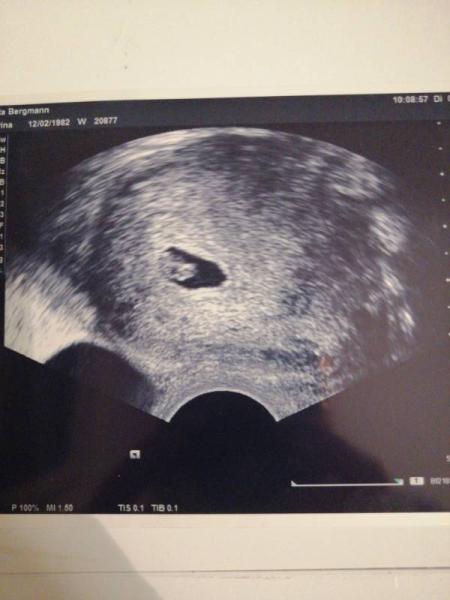

Hey, lieben Dank für deine Rückmeldung. Auch wenn ich mir ne andere Antwort gewünscht hätte. Ich hatte Im Oktober bereits eine fehlgeburt und brauche das nicht unbedingt nochmal. Ich hoffe halt sehr dass sich bei uns alles gut entwickelt. Meine Frauenärztin ist irgendwie dann auch gar nicht näher auf die fruchthöhle eingegangen. Meine hält nur in nem Nebensatz dass die fruchthöhle noch ein kleines Fragezeichen wäre, aber das herz auf jedenfall schlägt. Da ich auch überhaupt keinen Vergleich habe weiss ich gar nicht ob die fruchthöhle wirklich so klein ist. Kannst du dich noch erinnern wie das bei dir aussah? Ich hänge einfach mal mein Bild an. Und es freut mich sehr dass es bei euch ja dann doch recht schnell wieder geklappt hat. Sowas macht dann doch wieder Hoffnung. LG

Bild zu